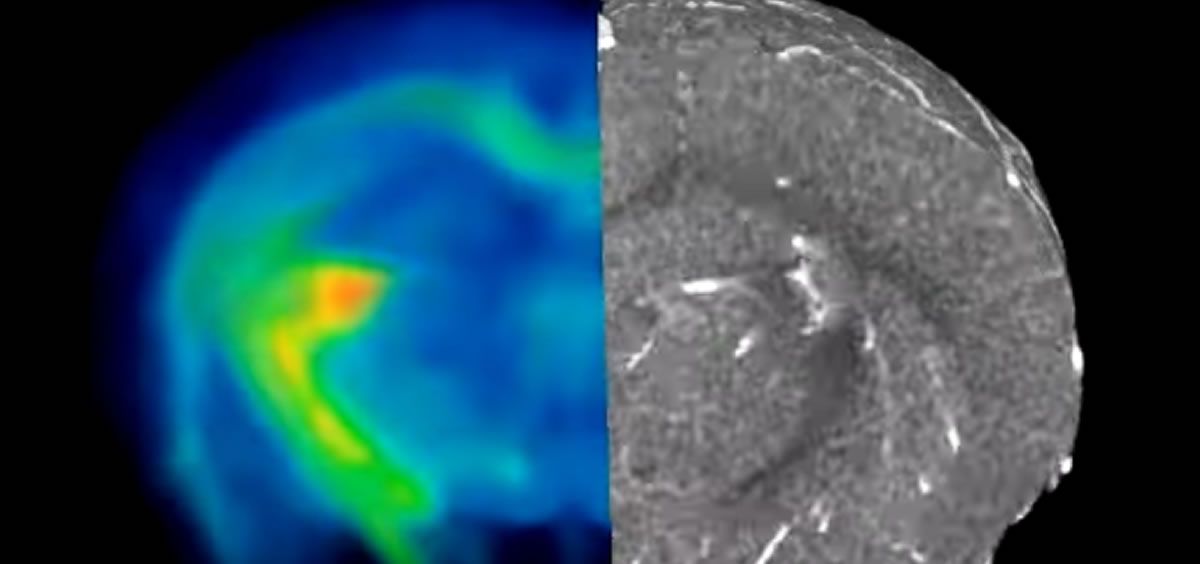

Esta técnica se basa en una combinación de agentes poliméricos que se pueden difundir en ese conjunto de vasos sanguíneos y conseguir así, obtener imágenes mediante microscopía óptica, resonancia magnética y tomografía computarizada (TC). La imagen combinada de estas técnicas crea mapas de tejido altamente detallados en diferentes escalas espaciales, consiguiendo información sobre los tipos de células y las estructuras de tejido que rodean los vasos sanguíneos.

El nombre del contraste que permite la obtención de imágenes de la misma muestra mediante los tres tipos de imágenes es VascuViz. Los componentes de este son un agente de contraste fluorescente para MRI llamado galbúmina-rodamina y un agente de contraste para TC llamado BriteVu. La mezcla de los polímeros permite obtener imágenes tanto de la microvasculatura como de la macrovasculatura.